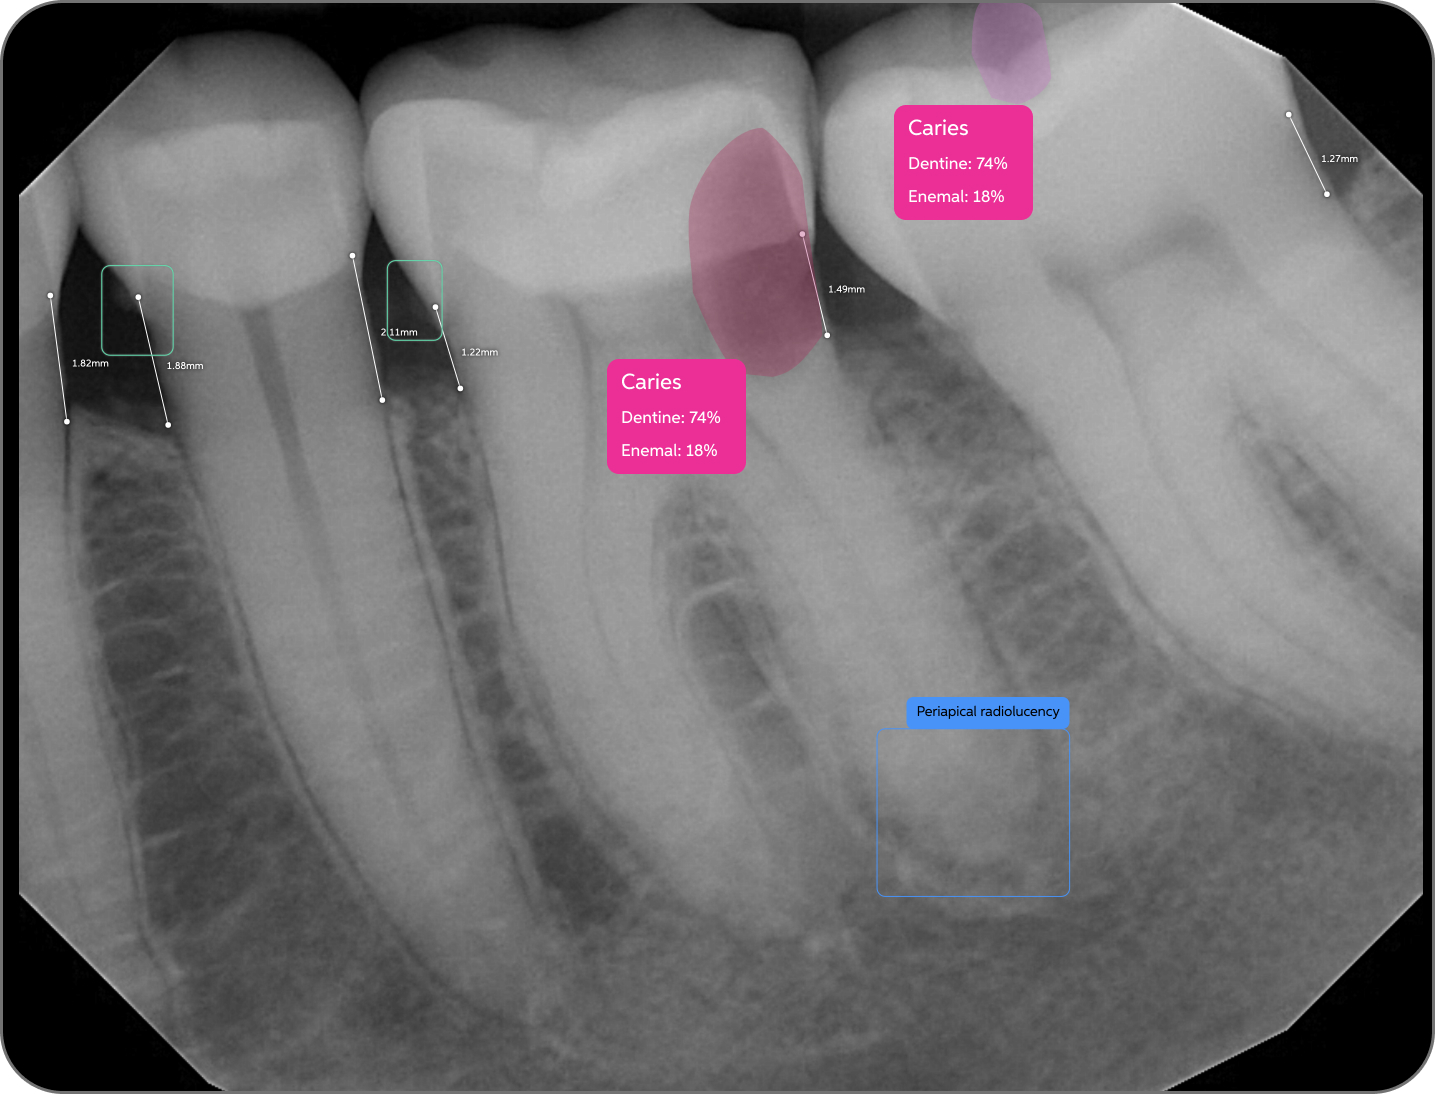

Pearl’s AI is trained on world's largest collection dental x-rays to detect a greater range of pathologies, existing restorations and natural anatomy than any solution of its kind, enabling 37% more accurate x-ray evaluations.

Color-coded detections, educational tooth part maps and quantitative results give patients an objective, clear and data-based foundation for trust in your findings––trust that boosts case acceptance by 24% on average.